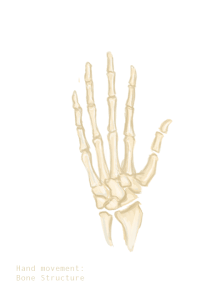

Illustration of hand and wrist bones

Bones of the left hand. Volar surface.

Bones of the left hand. Dorsal surface.- Static adult human physical characteristics of the hand

The skeleton of the human hand consists of 27 bones:[10] the eight short carpal bones of the wrist are organized into a proximal row (scaphoid, lunate, triquetral and pisiform) which articulates with the bones of the forearm, and a distal row (trapezium, trapezoid, capitate and hamate), which articulates with the bases of the five metacarpal bones of the hand. The heads of the metacarpals will each in turn articulate with the bases of the proximal phalanx of the fingers and thumb. These articulations with the fingers are the metacarpophalangeal joints known as the knuckles. At the palmar aspect of the first metacarpophalangeal joints are small, almost spherical bones called the sesamoid bones. The fourteen phalanges make up the fingers and thumb, and are numbered I-V (thumb to little finger) when the hand is viewed from an anatomical position (palm up). The four fingers each consist of three phalanx bones: proximal, middle, and distal. The thumb only consists of a proximal and distal phalanx.[11] Together with the phalanges of the fingers and thumb these metacarpal bones form five rays or poly-articulated chains.